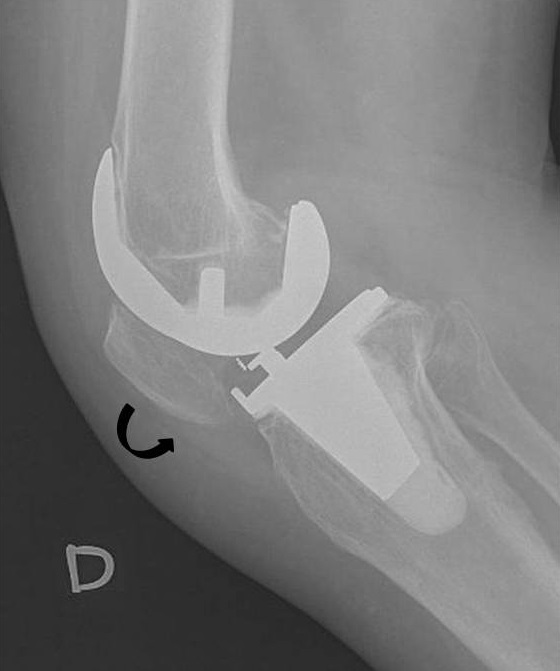

''슬개골 고위증(patella alta)''은 높이 위치한 무릎뼈를 의미한다. 약화된 슬개골 고위증(attenuated patella alta)은 관절 위에서 발달하는 비정상적으로 작은 무릎뼈이다.''슬개골 저위증(patella baja)''은 낮게 위치한 무릎뼈를 의미한다. 장기간 지속된 슬개골 저위증은 신전 기능 부전을 초래할 수 있다.[5]

''인설-살바티 비율''은 측면 X-ray에서 슬개골 저위증을 나타내는 데 도움이 되며, 슬개건의 길이를 슬개골의 길이로 나누어 계산한다. 인설-살바티 비율이 0.8보다 작으면 슬개골 저위증을 나타낸다.[6]